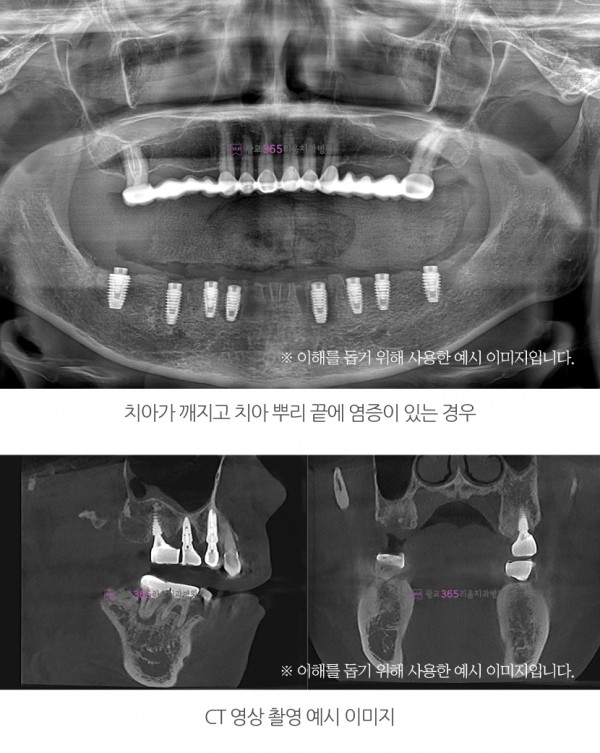

전체 임플란트 | 전체 임플란트, 꼭 해야 하나요?